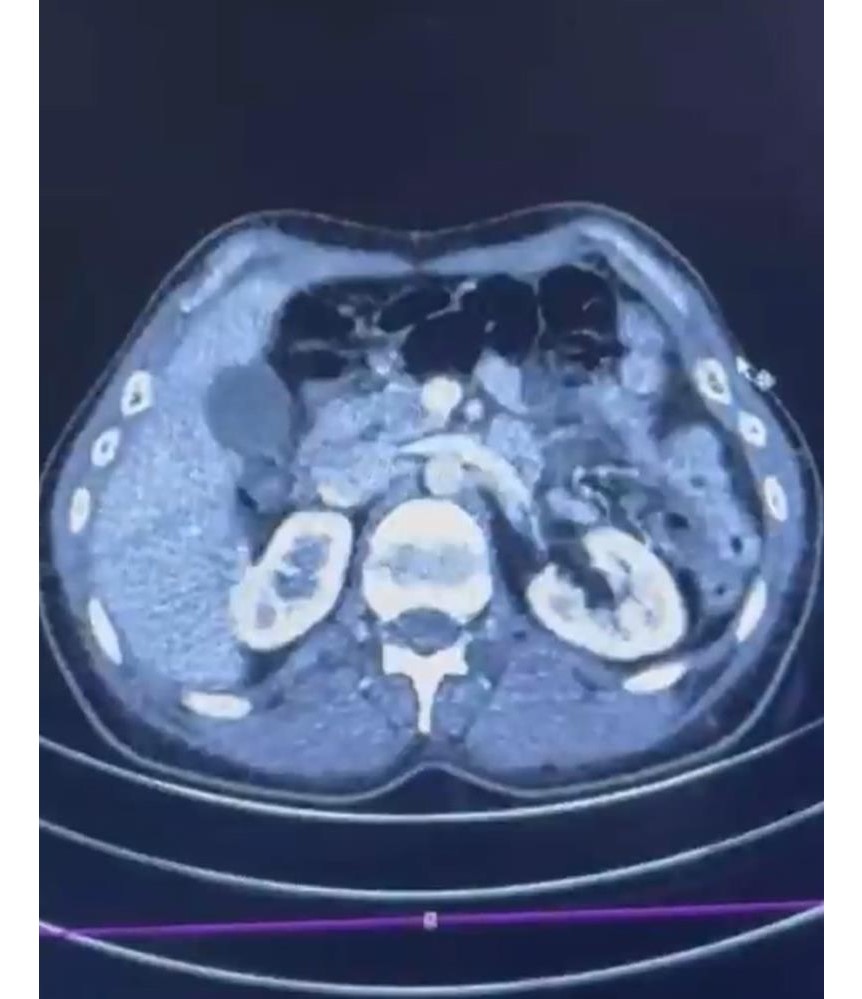

Şüphelilerden S.C. ile R.B.C., muayene için Kayseri Şehir Hastanesi’ne götürüldü. Burada yapılan röntgen ve ultrason kontrollerinde midelerinde kapsüller halinde uyuşturucu madde bulunduğu belirlendi. Sağlık ekiplerinin tedavisi eşliğinde çıkarılan kapsüllerden toplam 554 gram uyuşturucu elde edildi.